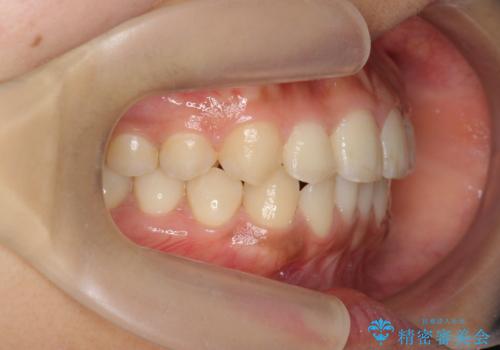

- 上下前歯のすれ違い、ねじれのある歯並びの矯正治療を求めて来院されました。

前歯のすれ違いが改善することで噛みやすくなった。と矯正治療の結果に満足いただくことができました。